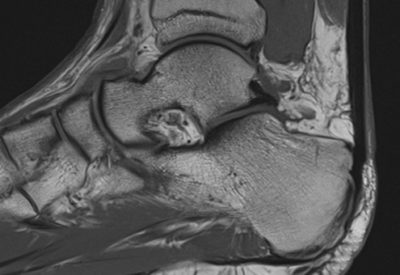

Hochwertige MRT-Untersuchung für maximale Diagnosesicherheit

Dann sind Sie bei uns richtig! Wir bieten Ihnen ein erfahrenes und spezialisiertes Ärzteteam, das MRT-Untersuchungen mit moderner Gerätetechnik durchführt. Unsere MRT-Untersuchungen sind optimiert und liefern hochauflösende Bilder, die eine maximale Diagnosesicherheit bieten.

Hochwertige MRT-Untersuchung für maximale Diagnosesicherheit

Dann sind Sie bei uns richtig! Wir bieten Ihnen ein erfahrenes und spezialisiertes Ärzteteam, das MRT-Untersuchungen mit moderner Gerätetechnik durchführt. Unsere MRT-Untersuchungen sind optimiert und liefern hochauflösende Bilder, die eine maximale Diagnosesicherheit bieten.